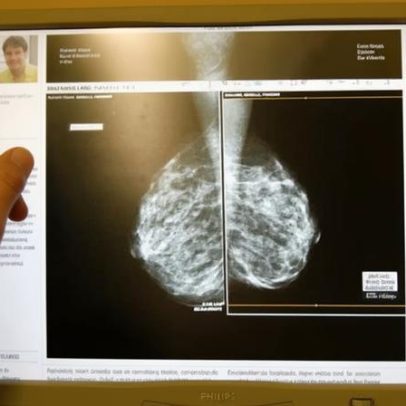

IA em triagem de câncer de mama reduz diagnósticos tardios em 12%

Uso de IA na mamografia reduz diagnósticos tardios em doze por cento e aumenta detecção precoce, mas exige avaliação criteriosa e monitoramento contínuo

IA em triagem de câncer de mama reduz diagnósticos tardios em 12%

há 5 meses